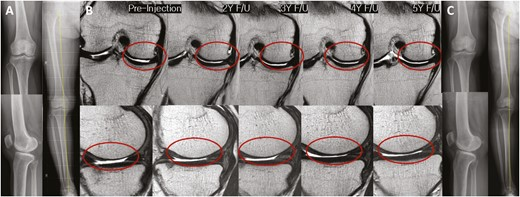

2022年5月14日,韓國江東慶熙大學(xué)醫(yī)院骨科在行業(yè)期刊《干細胞轉(zhuǎn)化醫(yī)學(xué)》上發(fā)表了一篇關(guān)于《關(guān)節(jié)內(nèi)注射間充質(zhì)干細胞治療膝骨關(guān)節(jié)炎的安全性和有效性:5年隨訪研究》的研究成果。【4】

招募了11名膝關(guān)節(jié)骨關(guān)節(jié)炎患者,并在單次關(guān)節(jié)內(nèi)注射自體高劑量 (1.0×108?) ADMSCs 的5年隨訪期間進行了系列評估。

- 系列MRI檢查顯示,注射后3年內(nèi)MFC軟骨缺損面積呈減少趨勢,治療后5年內(nèi)未見明顯惡化(圖 4)。

- 內(nèi)側(cè)間室軟骨WORMS評分在注射后2至3年間均有明顯改善(2年,P=0.029;3年,P=0.031)(表3)。

- 治療后3年內(nèi),總體WORMS顯示出顯著改善,從73.4±27.8顯著下降至70.5±26.8(6個月;P= 0.020)、65.5±29.4(2年,P=0.016)和66.5±30.7(3年,P=0.041)(表3)。

- WORMS子評分還顯示,在注射后2至3年內(nèi)、注射后2年內(nèi)和注射后3年內(nèi),總軟骨狀態(tài)、骨髓水腫和滑膜炎均有顯著改善。

綜上所述,VAS和總WOMAC評分在注射后6個月以及直到最新隨訪時均顯著改善。總WORMS在注射后3年內(nèi)顯著改善。

單次關(guān)節(jié)內(nèi)注射自體高劑量ADMSCs可在5年內(nèi)提供安全的臨床改善,且不會出現(xiàn)放射學(xué)加重。此外,骨關(guān)節(jié)炎膝關(guān)節(jié)的結(jié)構(gòu)變化在長達3年的時間內(nèi)顯示出顯著改善,這表明它可能是膝關(guān)節(jié)OA患者的疾病改良治療的一種可能選擇。